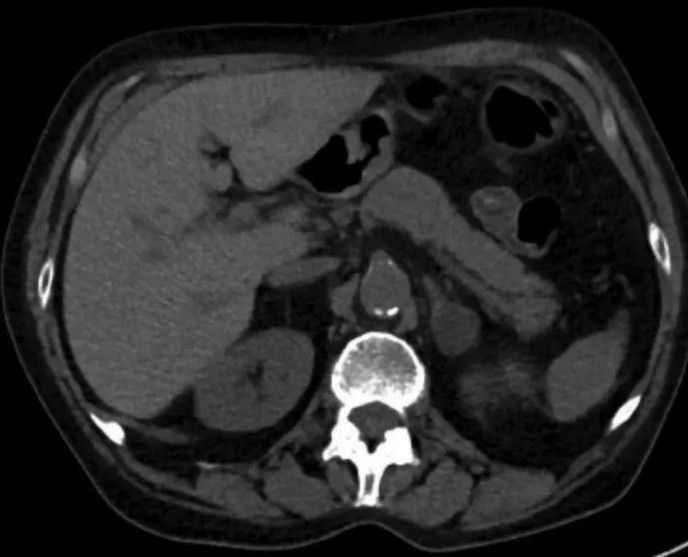

Is this calcification of abdominal aorta?